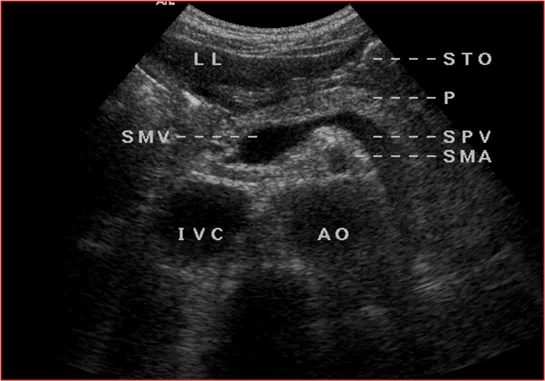

●胰腺长轴切面

标志为:胰腺后方脾静脉长轴。

应显示:胰头、胰颈、胰体、部分胰尾和主胰管。

利用标识血管来判断胰腺的位置

胰腺-长轴切面